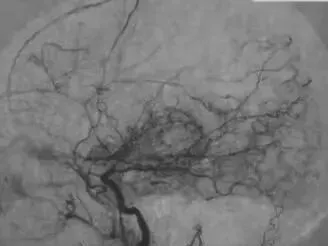

烟雾病属于一种罕见的脑血管疾病,其特征性表现为大脑主要血管(包括颈内动脉终末段以及大脑前动脉与大脑中动脉近端)出现进行性狭窄乃至完全闭塞。为了代偿由此引发的脑组织缺血,脑底部会形成大量纤细的异常血管网络。这些血管在脑血管造影影像中呈现为‘烟雾状’外观,该疾病因此得名。

【图片】